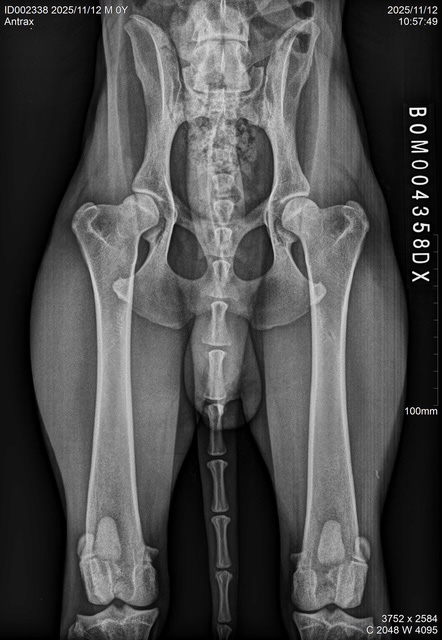

| ANTRAX, DOB July 2 2024, elbows/hips/spine: see x-rays below. ATRAX is almost 2 years old malinois male that was raised in the kennel. He is used to stay both inside the kennel as well as inside of house. He is good with other dogs and has no problem with other animals. ATRAX is a normal social dog and he gets used to the new handler and environment quickly. ANTRAX doesn't have problem with any kind of surface. ANTRAX has excellent ball drive. He is able to search for hidden ball in very hard environments and conditions. He searches with great interest and persistance until he finds the ball. His protection is also excellent. He has fast and hard bites. He is able to work inside and outside of buildings and he can bite on sleeve as well as bite suit. ANTRAX is suitable as a dog for personal protection or as a dual purpose law enforcement dog. |

X-RAYS: